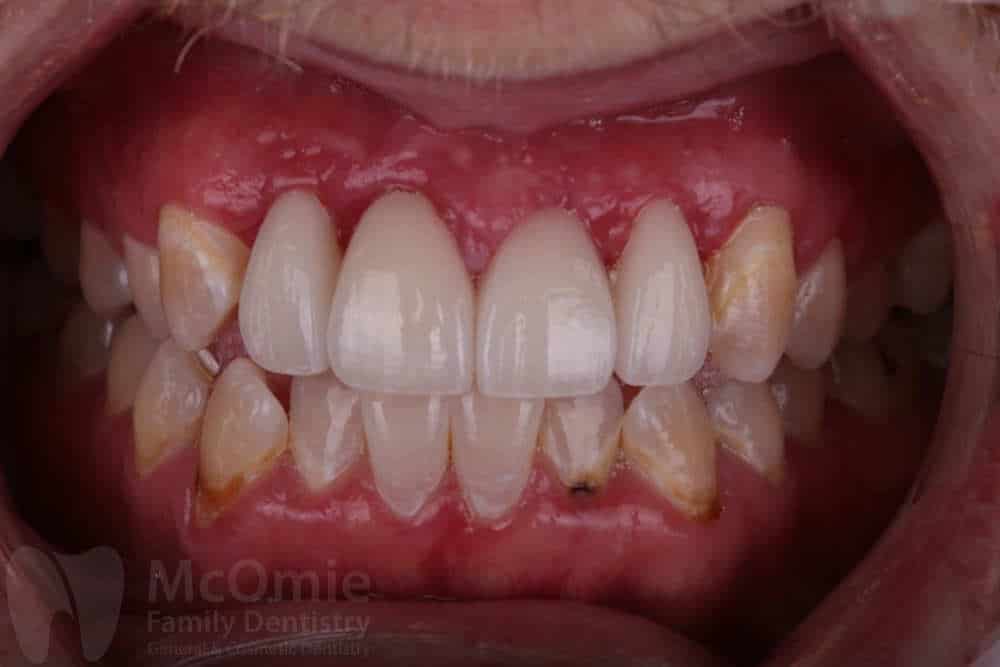

Case 19 – Dental Trauma

This case involved restoring two front teeth after a fall caused facial trauma and significant damage to the smile. The injury resulted in fractured front teeth and irregular gum contours. Treatment included placing two custom crowns along with gum contouring to refine the shape of the tissue and improve symmetry. The restorations were carefully crafted by our master ceramists to match natural tooth structure, color, and detail. The result is a seamless, natural-looking smile with both aesthetics and function fully restored.